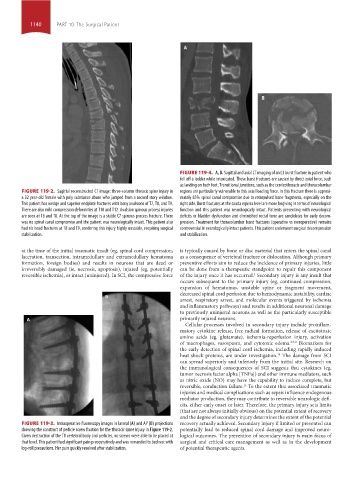

FIGURE 119-4. A, B. Sagittal and axial CT imaging of an L3 burst fracture in patient who

fell off a ladder while intoxicated. These burst fractures are caused by direct axial force, such

as landing on both feet. Transitional junctions, such as the cervicothoracic and thoracolumbar

FIGURE 119-2. Sagittal reconstructed CT image: three-column thoracic spine injury in regions are particularly vulnerable to this axial loading force. In this fracture there is approxi-

a 32 year-old female with poly substance abuse who jumped from a second story window. mately 85% spinal canal compromise due to retropulsed bone fragments, especially on the

This patient has wedge and superior endplate fractures with bony avulsions of T7, T8, and T9. right side. Burst fractures at the cauda equina level are more forgiving in terms of neurological

There are also mild compression deformities at T10 and T12. Avulsion spinous process injuries function and this patient was neurologically intact. Patients presenting with neurological

are seen at T6 and T8. At the top of the image is a stable C7 spinous process fracture. There deficits or bladder dysfunction and diminished rectal tone are candidates for early decom-

was no spinal canal compromise and the patient was neurologically intact. This patient also pression. Treatment for thoracolumbar burst fractures (operative vs nonoperative) remains

had rib head fractures at T8 and T9, rendering this injury highly unstable, requiring surgical controversial in neurologically intact patients. This patient underwent surgical decompression

stabilization. and stabilization.